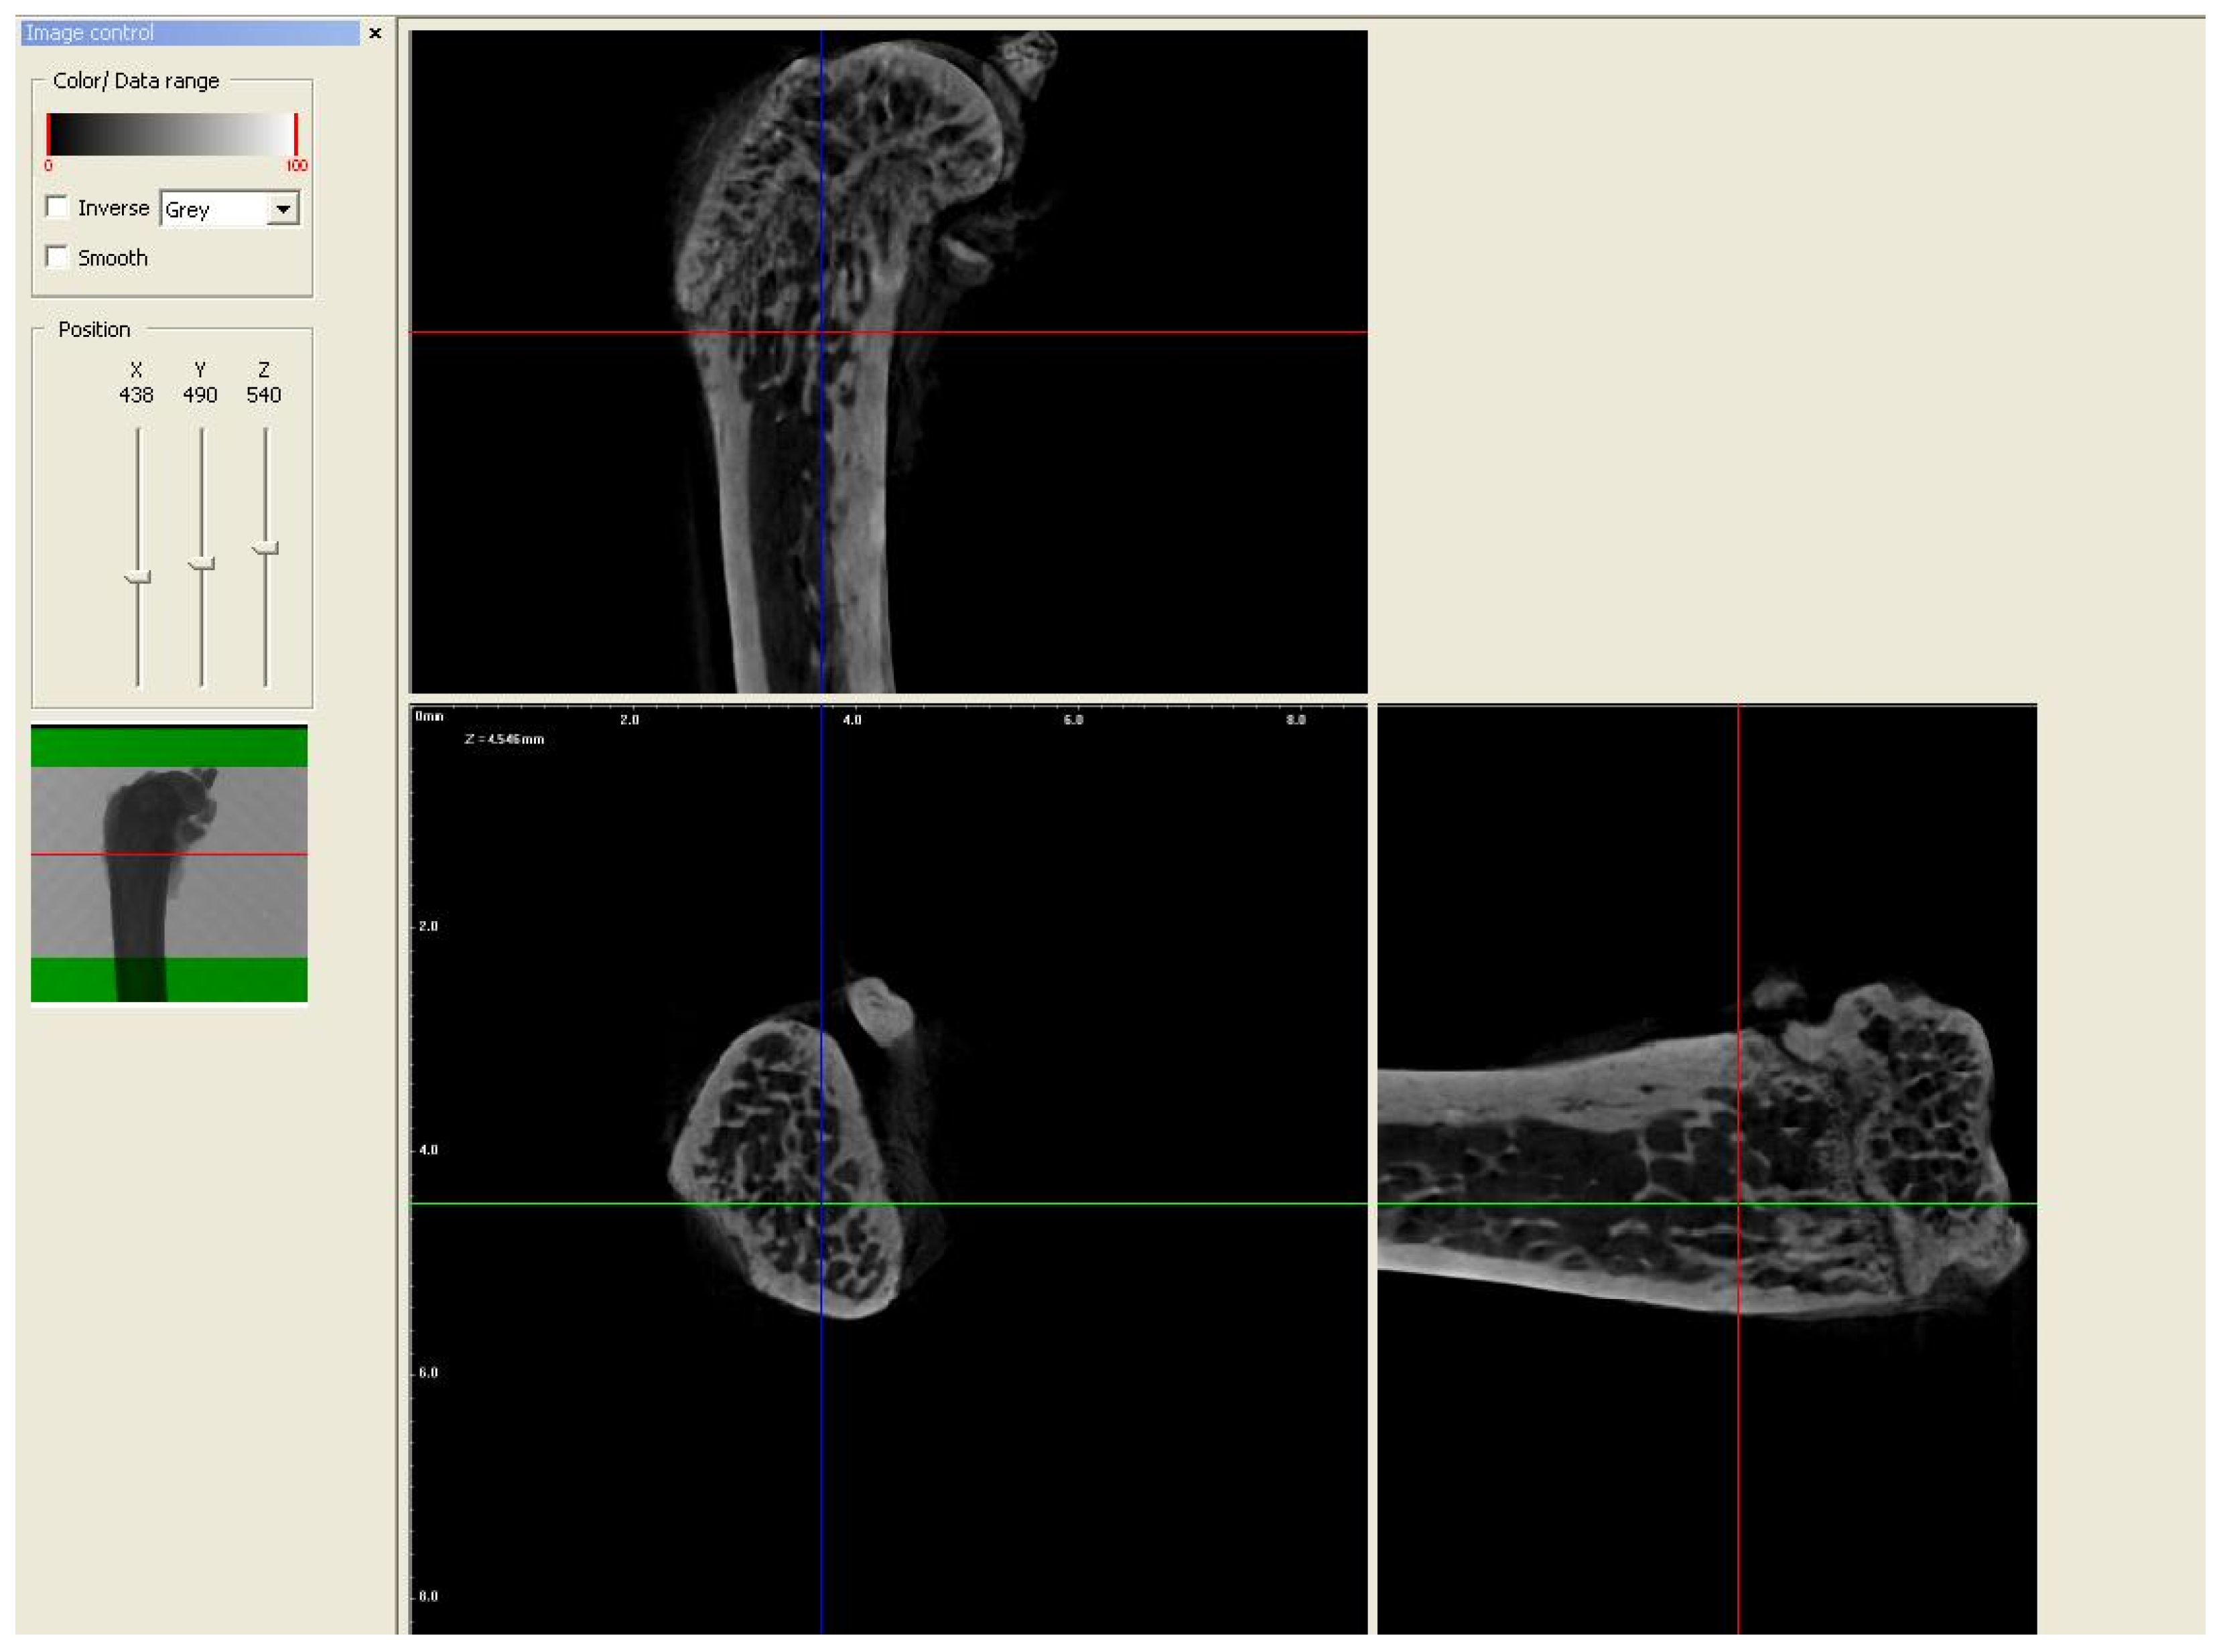

2.2. Micro-CT Analysis

3.3.1. Trabecular Thickness (Tb.Th), Trabecular Number (Tb.N), and Percent of Bone Volume (BV/TV)

3.3.2. Trabecular Separation

3.4. Cortical Bone Area